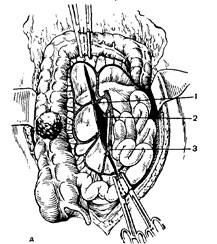

Kérelemre ileotransverzoanastomoza oldalán-oldalra anasztomózisok csípőbél hurkot keresztirányú-sósav vastagbél isoperistaltic, t. E. Végeiket két oldalán helyezkednek el (vége a vékonybélben mentén fekszik a vastagbél) (13.).

Ábra. 13. előírása csípőbél-transverzoanastomoza oldalról a másikra.

és - alakítás a hátsó fal-ki; b - alakítás elülső falának az anasztomózis.

Anastomosis oldalról a másikra kell helyezni a szabadságot távú szalag vastagbél a parttól 3-4 cm-re a végén a vezetékes és körülbelül 2 cm-re a végétől az ileum. Ennél intervallum bizonyos távolságot körülbelül 1 cm-re a szabad szalag vastagbél- és körülbelül 1 cm-re a mesenterialis szélén a vékonybél közötti egymásra hátsó sor csomóponti szerológiai izmos selyemöltéssel hosszasan-SRI b-7 cm mentén szabad szalag végét fonal tartó egyezés vesz egy Kocher bilincs, és a többi (köztük), CFE-zayut. Továbbá, a párhuzamosan száma szérum-izmos varratok a parttól 1 cm-re, kinyitotta az első az ileum üregébe, anélkül, hogy elérné a szélsőséges nor-tei-derzhalok 1-1,5 cm. Ezután a párhuzamos szakaszon az ileum nyitott lumen a vastagbélbe a közepén a szabad öv, korábban kiszabott enyhe bél bilincs a kapott al-szegmens vzdoshnoy belek nyílásánál a lumen a bél béltartalom nem áramlik be a hasüregbe. Így a teljes szélessége anastomo kialakított egyik oldalról a másikra körülbelül 4 cm-es, amely szabad mozgását a béltartalom a vékonybélből a

vastag. Belső varratok számlálni cherezvseobolochki helyezett folytonos twining kerek catgutból varrat vagy jobb csomóponti selyem öltésekkel, a külső sor (szérum-izmos varróanyag) szabhat csomóponti selyem varratokat. Ileumbeli hurok mindkét oldalán Anastacia-Mócza tovább erősítve a vastagbél egy két hálószobás - három csomóponti selyem varratokkal mindkét oldalon. Ebben a formáció ileotransverzoanastomoza befejeződött. Az élek a bélfodra a vastagbél és a vékonybél sshi-vayut csomóponti selyem öltésekkel, hogy a különbség köztük, és nem tudtam, hogy sértik a vékonybélben körök. A hiba a hátsó fal a hashártya a helyén a távoli-zling bél megszüntesse varrás élek hashártya alulról felfelé folyamatosan catgut. Benyújtásának eltávolítását a vastagbél mellékelt dréncső, amely kiadási négy res külön metszést a jobb ágyéki vagy podvzdosh távú mezőt és rögzítve a bőrt 1-2 selyemmel VYM varratok. Laparotomia sebet összevarrtuk rétegesen. Funkcionálisan előny invaginated ileotransver zoanastomoz-in oldali vége a vékony-tol állvány bélben, amely megakadályozza, hogy a lehető ob önzetlen dobott gyomorpépet keresztül az anastomosis a obodoch-sósav bélből a csípő.